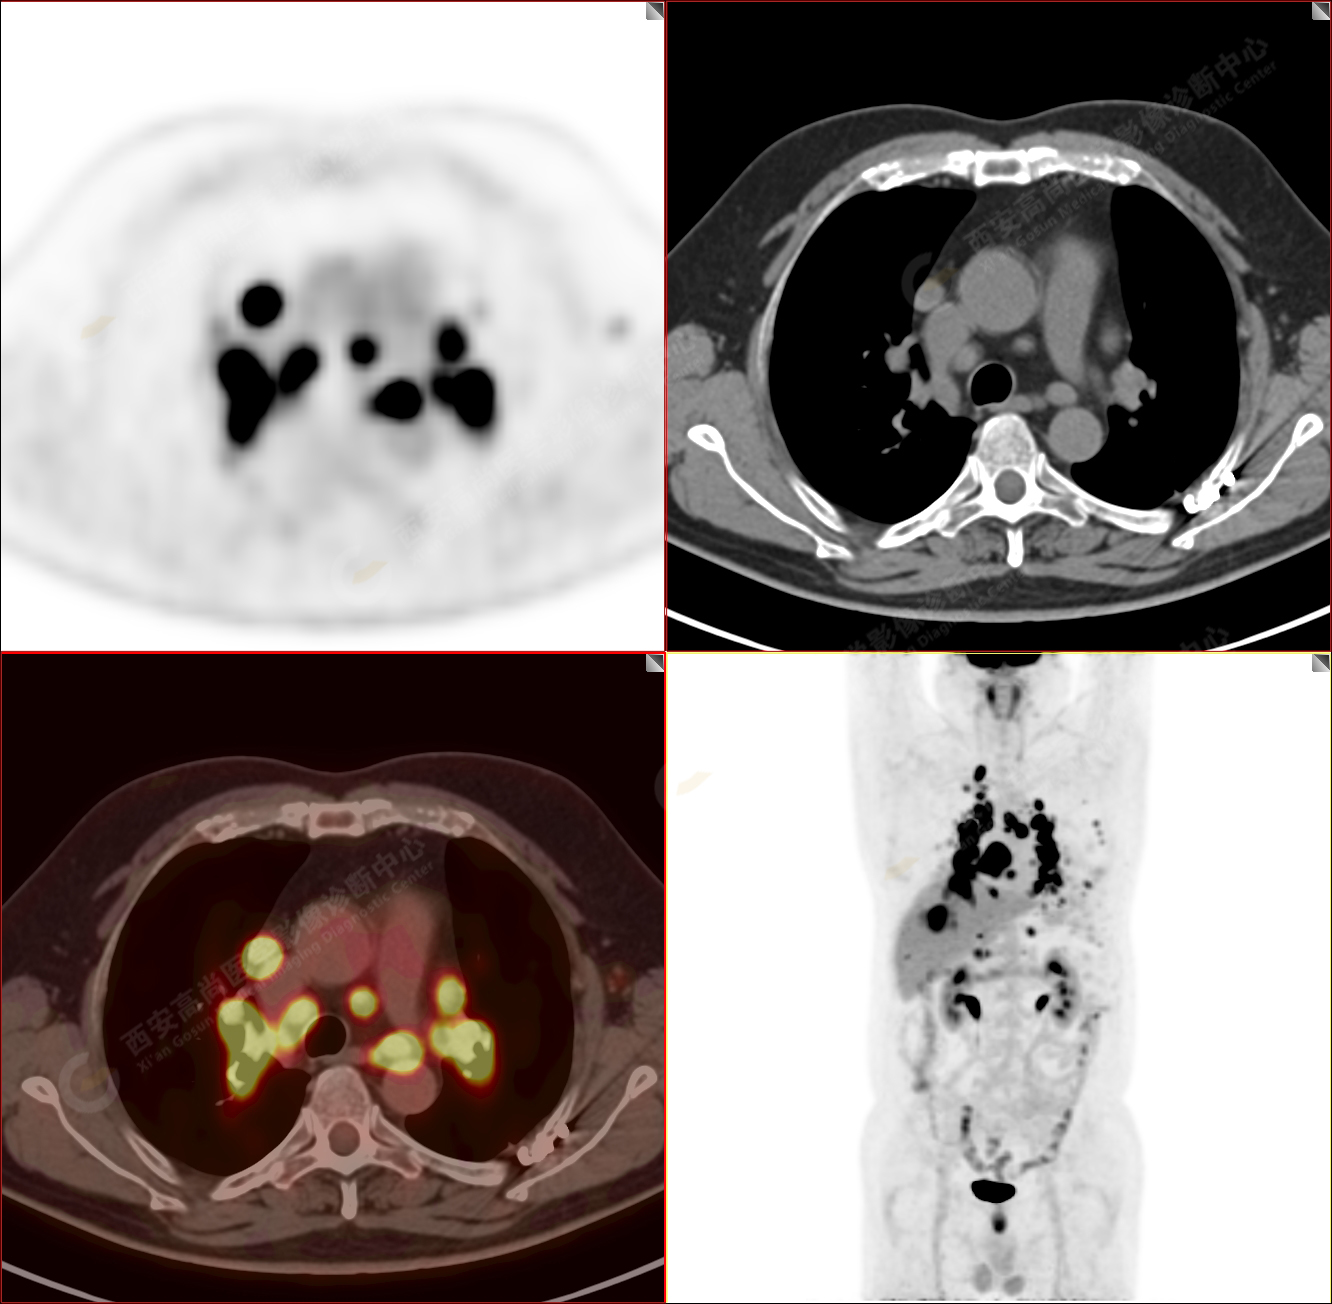

男性,53歲,頭暈半月入院,CT發(fā)現(xiàn)肺內(nèi)腫塊,雙肺多發(fā)大小不等實(shí)性及粟粒樣結(jié)節(jié),雙肺門(mén)及縱隔多發(fā)腫大淋巴結(jié)。病程中無(wú)發(fā)熱、胸悶氣及胸部不適。既往:左側(cè)肋骨外傷史。

PET/CT圖像